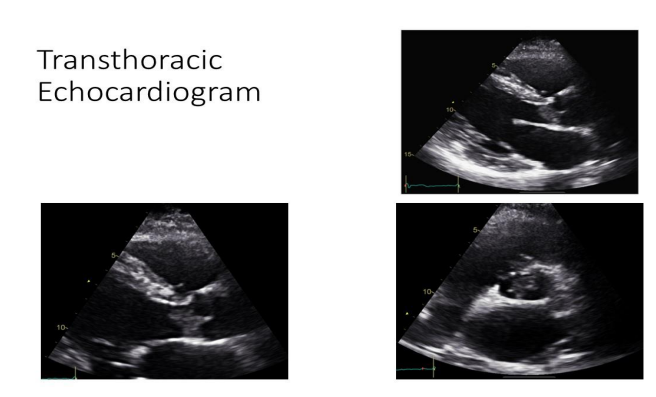

Echocardiography

A transthoracic echocardiogram, conducted as part of her routine stroke workup, revealed:

• A large aortic valve mass

• Moderate eccentric aortic regurgitation

• Absence of left ventricular outflow tract (LVOT) obstruction

Figure 3